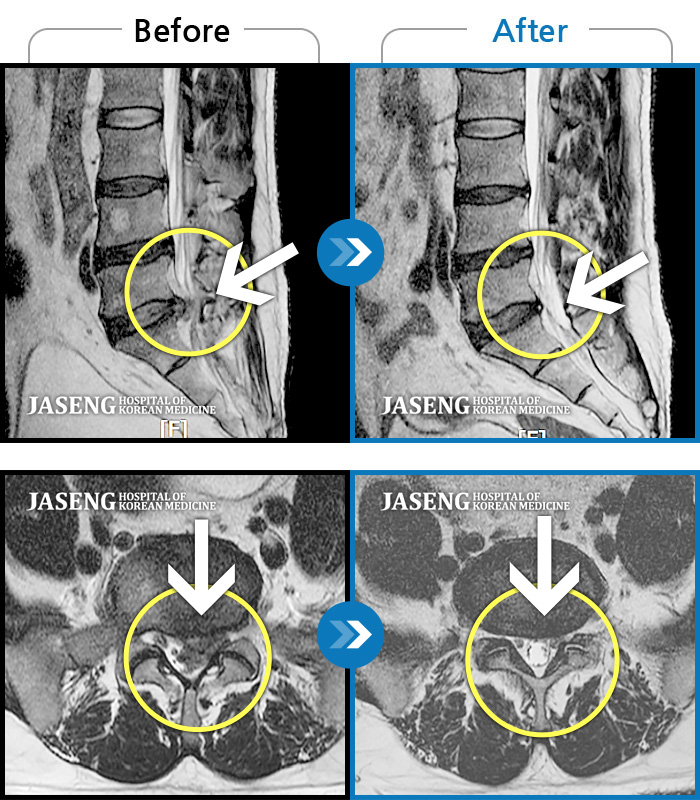

허리디스크

인천 · 조남훈 원장

좌측 허벅지와 종아리가 찌릿하고 묵직한 통증이 있어요.

촬영시기

2025.03.18 ~ 2025.07.22

2025.08.01